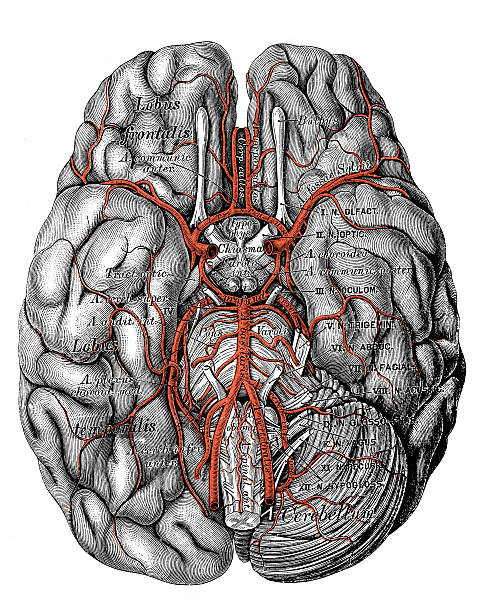

뇌동맥류는 뇌의 혈관이 벽의 약한 부분이나 손상으로 인해 팽창하거나 부풀어 오른 상태를 말합니다. 뇌동맥류는 일반적으로 증상이 없으며, 우연히 발견되기도 합니다. 그러나 뇌동맥류가 크거나 위치가 민감한 경우, 심각한 증상을 초래할 수 있어 이번 시간에는 뇌동맥류로 나타나는 증상에 대해 자세히 알아보도록 하겠습니다.